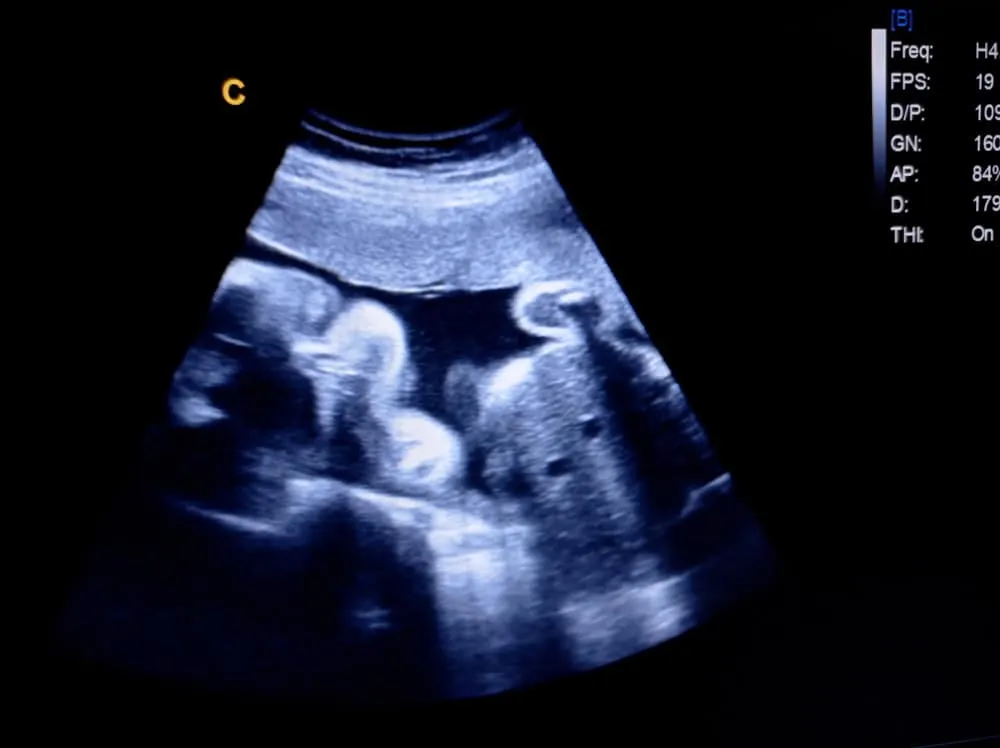

2. Hình ảnh siêu âm thai 28 tuần

Các chỉ số thai 28 tuần cụ thể như sau:

- Đường kính lưỡi đỉnh (BPD): 64-78mm

- Chiều dài xương đùi (FL): 48-57mm

- Chu vi vòng đầu (HC): 243-283mm

- Chu vi vòng bụng (AC): 215-264mm.